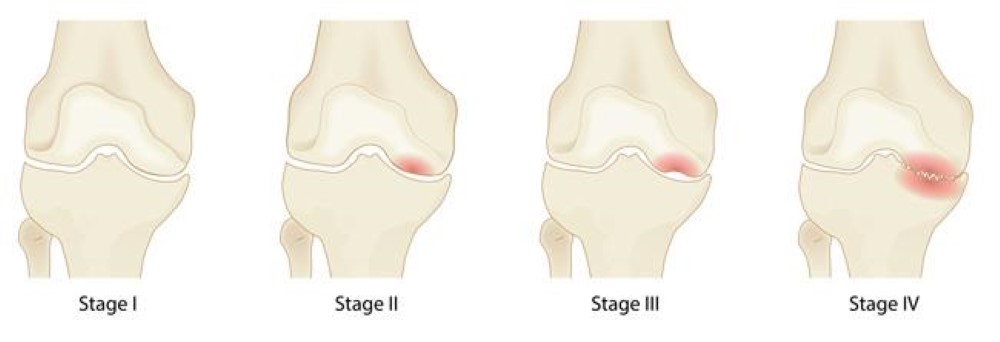

The four stages of osteonecrosis of the knee. The disease can progress from a normal, healthy knee (Stage 1) to the collapse of the bone and severe osteoarthritis (Stage 4).

Osteonecrosis progresses through several stages, each with distinct symptoms:- Early Stage: The initial sign is often a sudden onset of pain on the inside of the knee, which may be triggered by a specific activity or a minor injury.

- Progressive Stage: As the condition worsens, standing, bearing weight, and moving the affected knee become increasingly painful.